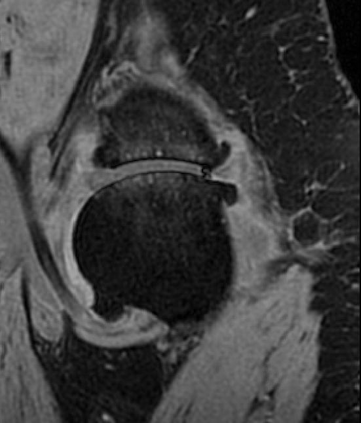

Magnetic resonance (MR) images are often acquired in 2D settings for real clinical applications. The 3D volumes reconstructed by stacking multiple 2D slices have large inter-slice spacing, resulting in lower inter-slice resolution than intra-slice resolution. Super-resolution is a powerful tool to reduce the inter-slice spacing of 3D images to facilitate subsequent visualization and computation tasks. However, most existing works train the super-resolution network at a fixed ratio, which is inconvenient in clinical scenes due to the heterogeneous parameters in MR scanning. In this paper, we propose a single super-resolution network to reduce the inter-slice spacing of MR images at an arbitrarily adjustable ratio. Specifically, we view the input image as a continuous implicit function of coordinates. The intermediate slices of different spacing ratios could be constructed according to the implicit representation up-sampled in the continuous domain. We particularly propose a novel local-aware spatial attention mechanism and long-range residual learning to boost the quality of the output image. The experimental results demonstrate the superiority of our proposed method, even compared to the models trained at a fixed ratio.

翻译:磁共振图像通常在 2D 环境中获得,用于真正的临床应用。通过堆叠多个 2D 切片重建的 3D 体积具有很大的切片间距,导致切片间分辨率低于切片分辨率。超级分辨率是减少3D 图像间隔的有力工具,以便利随后的可视化和计算任务。然而,大多数现有工程都以固定比例对超级分辨率网络进行培训,这在临床场景中不方便,因为MR 扫描的参数各异。在本文中,我们提议建立一个单一的超级分辨率网络,以任意调整比例降低MR 图像的切片间间间距。具体地说,我们将输入图像视为坐标的一个连续的隐含功能。不同间距比率的中间切片可以按照连续域内隐含的显示比例来构造。我们特别提议了一个新的地方觉空间关注机制和远程留置学习,以提高输出图像的质量。实验结果显示我们拟议方法的优越性,即使与所培训的模型相比,也是一种固定比例。